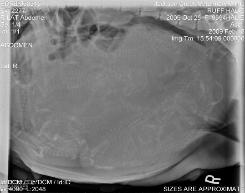

Weekly Report *Just Born* 2-18-09 6 Females 4 Males Wish us good health over the next few days ^^^^^^^^ 5 Days old 9 DAYS Old 1 Week old 2 weeks old Our eyes are just starting to open and we are walking pretty good for not being able to see yet. 3 weeks This is the 2 girls that live with Hopper's baby 3 weeks 3 1/2 Weeks 4 weeks We have our collars on now 5 weeks 6 weeks old CLICK HERE FOR INDIVIDUAL SHOTS OF EACH PUP 7 WEEKS 8 WEEKS |